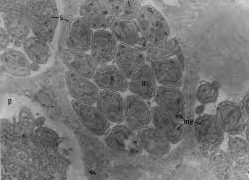

コクシジウム症 ~ 周囲の環境から胞子形成オーシスト(コクシジウム「卵」)を摂取することにより感染します

病名コクシジウム症病因アリメリア原虫主な宿主鶏発症日齢全日齢病気の伝播平飼いでは速い、水平死亡率E,Etenella, E,necatrixでは高い症状急性盲腸コクシジウム症:血便、貧血急性小腸コクシジウム症:大量の粘血便を排出して死亡慢性...